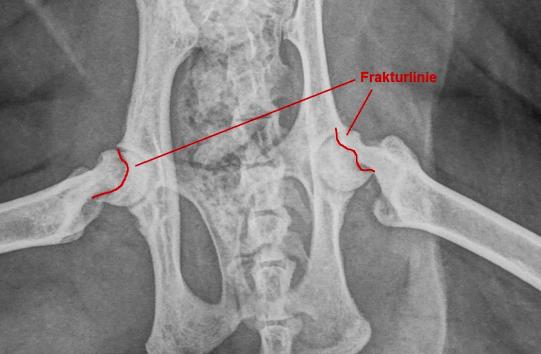

Charly wird orthopädisch untersucht. Er zeigt ein stark verändertes Gangbild in der Hinterhand: Die Katze läuft mit gekrümmtem Rücken, untergeschobenen Hinterbeinen und wie auf Eiern. Die Oberschenkelmuskulatur ist beidseits schlecht ausgebildet, und das Strecken der Hüftgelenke ist ganz offensichtlich schmerzhaft. In einer kurzen Sedation werden deshalb Röntgenaufnahmen des Beckens und der Hüftgelenke angefertigt. Hier ist die Ursache des Problems ersichtlich: An beiden Oberschenkelhälsen ist eine Bruchlinie zu sehen; die Oberschenkelköpfe sind beidseits vom Oberschenkelhals-Knochen abgebrochen!

Die Röntgenveränderungen erklären die Gangprobleme von Charly vollständig - er leidet unter einer beidseitigen sogenannten metaphysealen Osteopathie der Oberschenkelhälse.